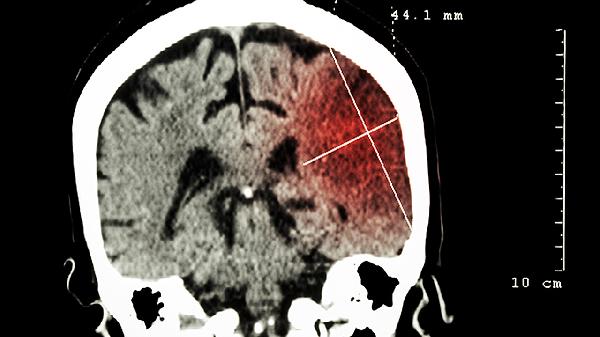

脑癌是会出現头痛的问题,出現症状的患者能够到医院门诊检查,剖析实际的病情,做个头部的CT查验,避免耽搁病情,适度的健身运动,增强机体抵抗能力,饮食搭配要以口味淡而颇具营养成分主导,培养良好习惯,有规律性的衣食住行,针对控制病情是有协助的。

颅内的肿瘤是会造成压迫症状,引起颅内压增高,可以引起头痛的症状,还伴有恶心呕吐等症状,偏头痛有可能是神经性偏头痛或三叉神经痛的原因造成的,必要时可以做头CT或核磁检查。